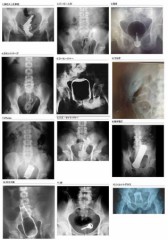

医者も状況確認できないと傷付ける危険性が在ればレントゲンで確認したりするようで

膣以外にも膀胱に体温計だとかアナルに電球だとか

『大事件に発展することも!おしりの異物の原因でうそをついてはいけない理由。嘘のような本当の話。おしりの異物から発展した大事件』等、検索すれば医療現場で大事件になる肛門は管腔臓器です。